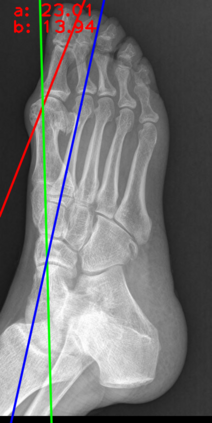

Angular measurements is essential to make a resonable treatment for Hallux valgus (HV), a common forefoot deformity. However, it still depends on manual labeling and measurement, which is time-consuming and sometimes unreliable. Automating this process is a thing of concern. However, it lack of dataset and the keypoints based method which made a great success in pose estimation is not suitable for this field.To solve the problems, we made a dataset and developed an algorithm based on deep learning and linear regression. It shows great fitting ability to the ground truth.